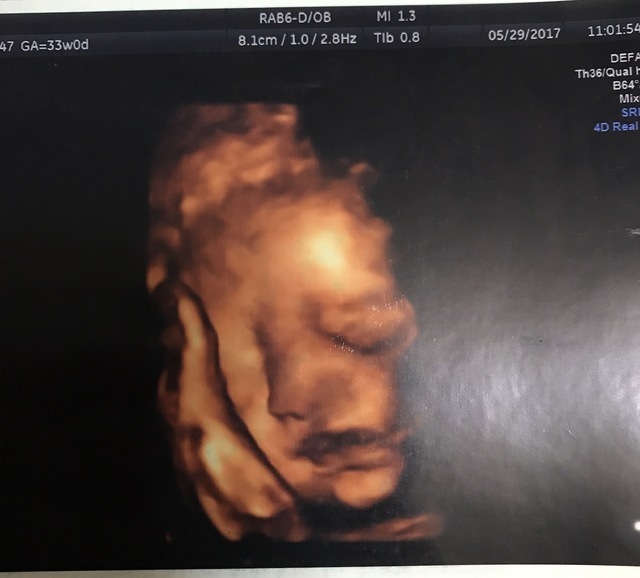

33週0日(33w0d・男の子)|るいちょん さん(23歳)

エコー写真撮影時のエピソード:

里帰り出産をするため地元の病院に初めて行って顔がはっきり見えました(^-^)

こんなにはっきり見えたのは初めてでわぁ!と声がでてしまいました笑

33週に入るとお腹も重たくなってきて動くのが大変に…。

33週に入った日から疲労と夜中何度か起きるため眠気が凄いです( .. )